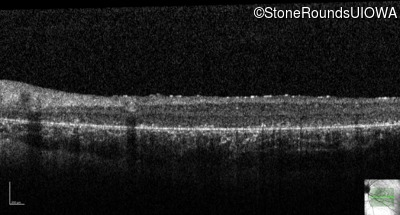

Optical Coherence Tomography - Right - 5/200

Exemplar / OCT Stack